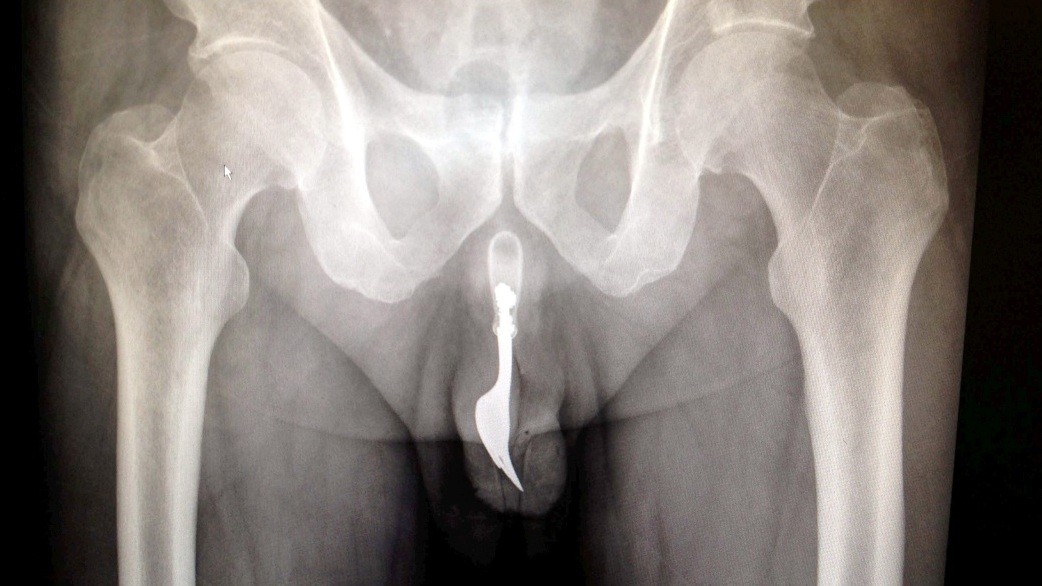

CANBERRA / Keď lekári prijali na pohotovosti v Austrálii staršieho pacienta, ktorý sa sťažoval na krvácanie z pohlavného orgánu, to ešte netušili, čo mu v ňom nájdu. Rontgenová snímka ich musela šokovať! V penise mal totiž strčenú 10 cm dlhú, oceľovú kuchynskú vidličku! A pravda o tom, ako sa mu tam dostala, nenechala na seba dlho čakať...

Lekári z austrálskej Canberry sa rozhodli zverejniť jeden z kontroverzných prípadov, kedy z pacientovho tela museli chirurgicky odstraňovať cudzí objekt. Nielen z tela, ale rovno z jeho pohlavného orgánu! Išlo pritom o 70-ročného muža, ktorý sa napokon ku všetkému priznal.

Podľa lekárskej správy, ktorú zverejnil denník The Daily Mail, sa muž chcel sexuálne uspokojiť, no jeho sexuálne dobrodružstvo vypálilo horšie, než čakal. Vidlička mu totiž ostala strčená v tele a spôsobila obrovské bolesti. Aj napriek nim sa však zahanbený dôchodca odvážil lekársku pomoc vyhľadať až o 12 hodín! Lekári muža napokon uspali a vidličku odstránili aj za použitia lubrikantu a pinzety... Procedúra bola úspešná a krátko po operácii mohol muž opustiť bez vážnych následkov nemocnicu.